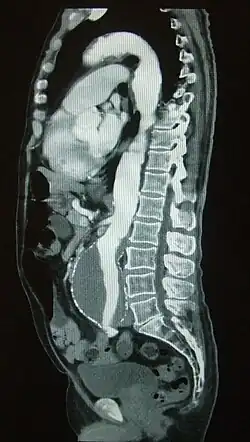

Болюсное контрастное усиление — один из наиболее распространённых методов контрастного усиления в компьютерной томографии, посредством внутривенного введения автоматическим инъектором контрастного препарата со скоростью от 2 до 7 мл в секунду. С этой целью применяют, как правило, неионные йодсодержащие препараты из расчета 2 мл на 1 кг массы обследуемого. Данный метод позволяет оценивать структуру сосудов (КТ-ангиография), выявлять и оценивать поражение паренхиматозных органов и др.

Болюсное контрастное усиление представляет собой механически управляемую инъекцию контрастного препарата посредством мощного шприца-инъектора с установленной скоростью введения (в большинстве случаев неизменной в ходе исследования). Такой характер введения контрастного препарата позволяет получить оптимальные для различных целей фазы контрастирования.

Фазы контрастирования непосредственно связаны со анатомией и физиологией кругов кровообращения и кровоснабжением органов (см. Круги кровообращения человека). Время задержки после начала введения контрастного препарата перед началом КТ-сканирования выбирается с учётом органа, представляющего собой цель изучения. Большинство органов имеют артериальное кровоснабжение. Исключение представляют собой печень и лёгкие (печень кровоснабжается не только из системы воротной вены — 75-90 %, но и из печёночной артерии; лёгкие получают венозную и артериальную кровь из малого и большого кругов кровообращения, соответственно). Органы, имеющие преимущественно артериальную перфузию, наиболее хорошо накапливают контрастный препарат через 5-15 секунд после пика контрастного усиления аорты. Печень предпочтительно сканировать в портальную фазу, в которую отмечается контрастирование органа и из системы печёночной артерии, и из системы воротной (портальной) вены. Для улучшения качества диагностики сканирование в портальную фазу контрастирования лучше предварить сканированием в артериальную фазу.